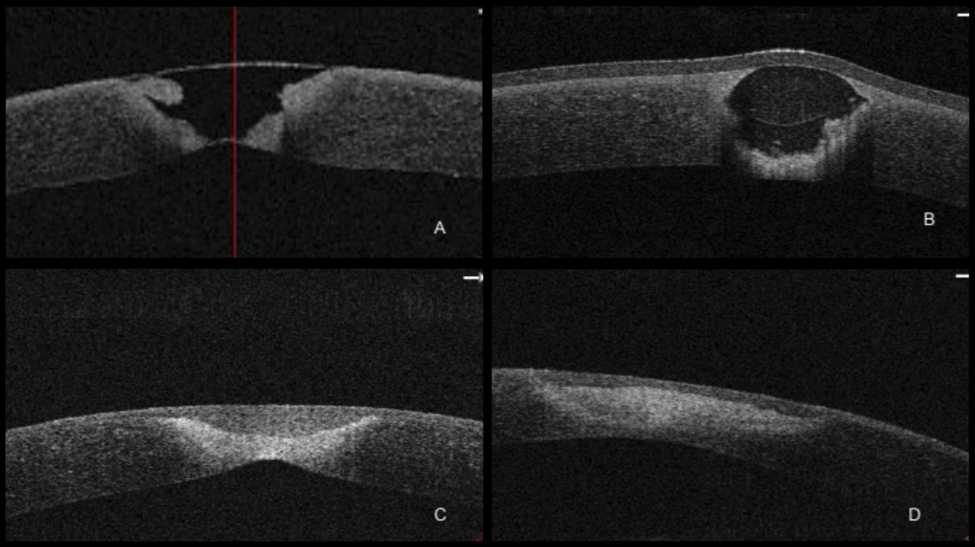

Figure 2. Anterior Segment Optical Coherence Tomography (OCT) imaging of the cornea A) Right corneal ulcer and descemetocele at initial presentation. B) Left corneal ulceration following placement of corneal glue and bandage contact lens. C) and D) Right and left corneal stroma, respectively, following treatment.

Over the course of eight months, the corneal stroma thickened and the fibrin glue was extruded bilaterally (Figure 1F-G. & Figure 2.) The pyogenic granuloma of the right eye resolved spontaneously. The patient underwent lacrimal punctal occlusion to aid in aqueous tear retention and continues to have frequent meibomian gland expression during subsequent follow up visits. The patient’s best corrected visual acuity recovered from 20/70 and 20/80 in the right and left eyes, respectively, at initial presentation to 20/20 and 20/30 in the right and left eyes, respectively.